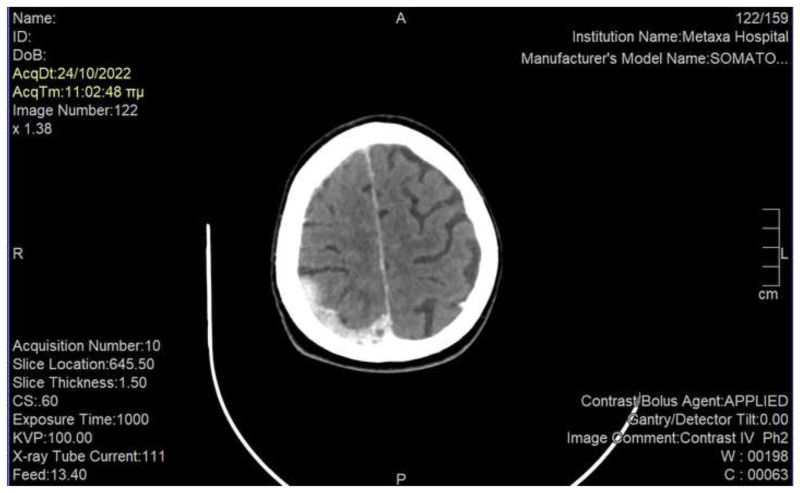

Phantosmia belongs to the group of olfactory dysfunctions. It is more commonly described in psychiatric conditions and some cases of viral infections, but it has been also rarely described in cancer patients who develop primary or metastatic central nervous system tumors; the early identification of this symptom in this population is crucial, as it could lead to timely diagnosis and treatment through a multidisciplinary approach. With the current report we present the case of a 60-year-old lady with metastatic breast cancer and without known preexisting brain metastases, who developed acute phantosmia without other neurological deficits; computed tomography of the brain revealed multiple brain metastases, which were attributed to the malignancy, and for which she was effectively treated with whole brain irradiation and antipsychotic as well as anticonvulsant medications. Furthermore, we underline the value of cooperation between the various specialties that could aid in diagnosis and management of this symptomatology. Phantosmia is an extremely rare symptom in cancer patients, and its appearance should alarm physicians to rapidly investigate a possible progression of disease in the central nervous system. Multidisciplinary approach is needed for the optimal management of these patients.